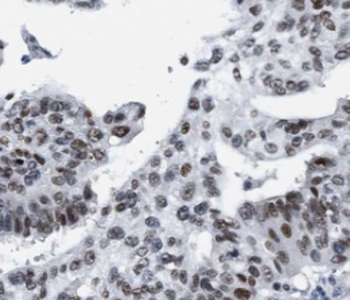

Immunohistochemistry of paraffin-embedded human ovary tumor slide using orb395161 (HuR Antibody) at dilution of 1:50.